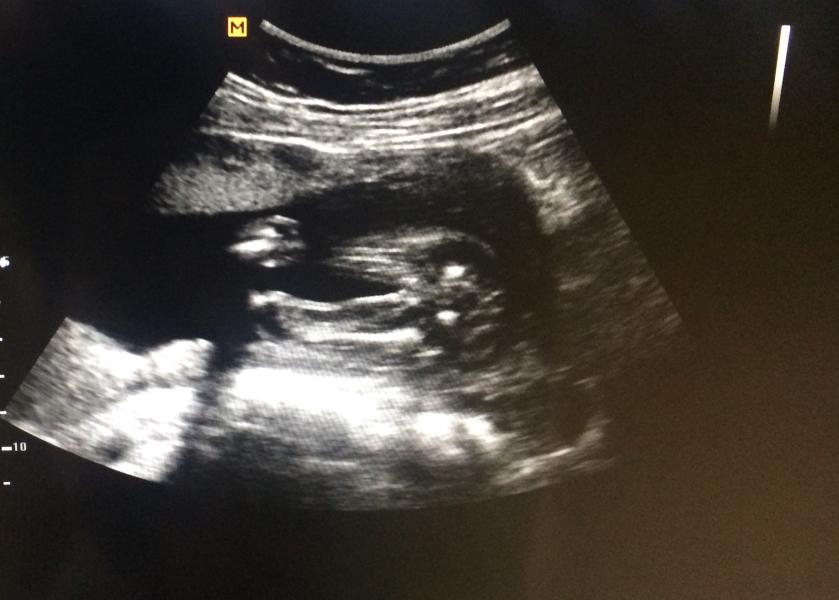

Сегодня проходила 2-й скрининг у Устиновой.И теперь уже 100% видно,что у меня будет ещё одна доченька.Счастью нет предела!!!Единственное крепко сидит на попе,так и не поняла,стоит ли уже беспокоиться,ведь срок то ещё маленький?Сама уже и не помню,когда и как мои переворачивались.У кого как?

Мне в 12 она сказала 99% девочка, сама в шоке, что на таком сроке определили. Устинова супер👍

@katherine_48, мне предварительно сказали в 16 неделек пол,но вот так как на фото не видно было